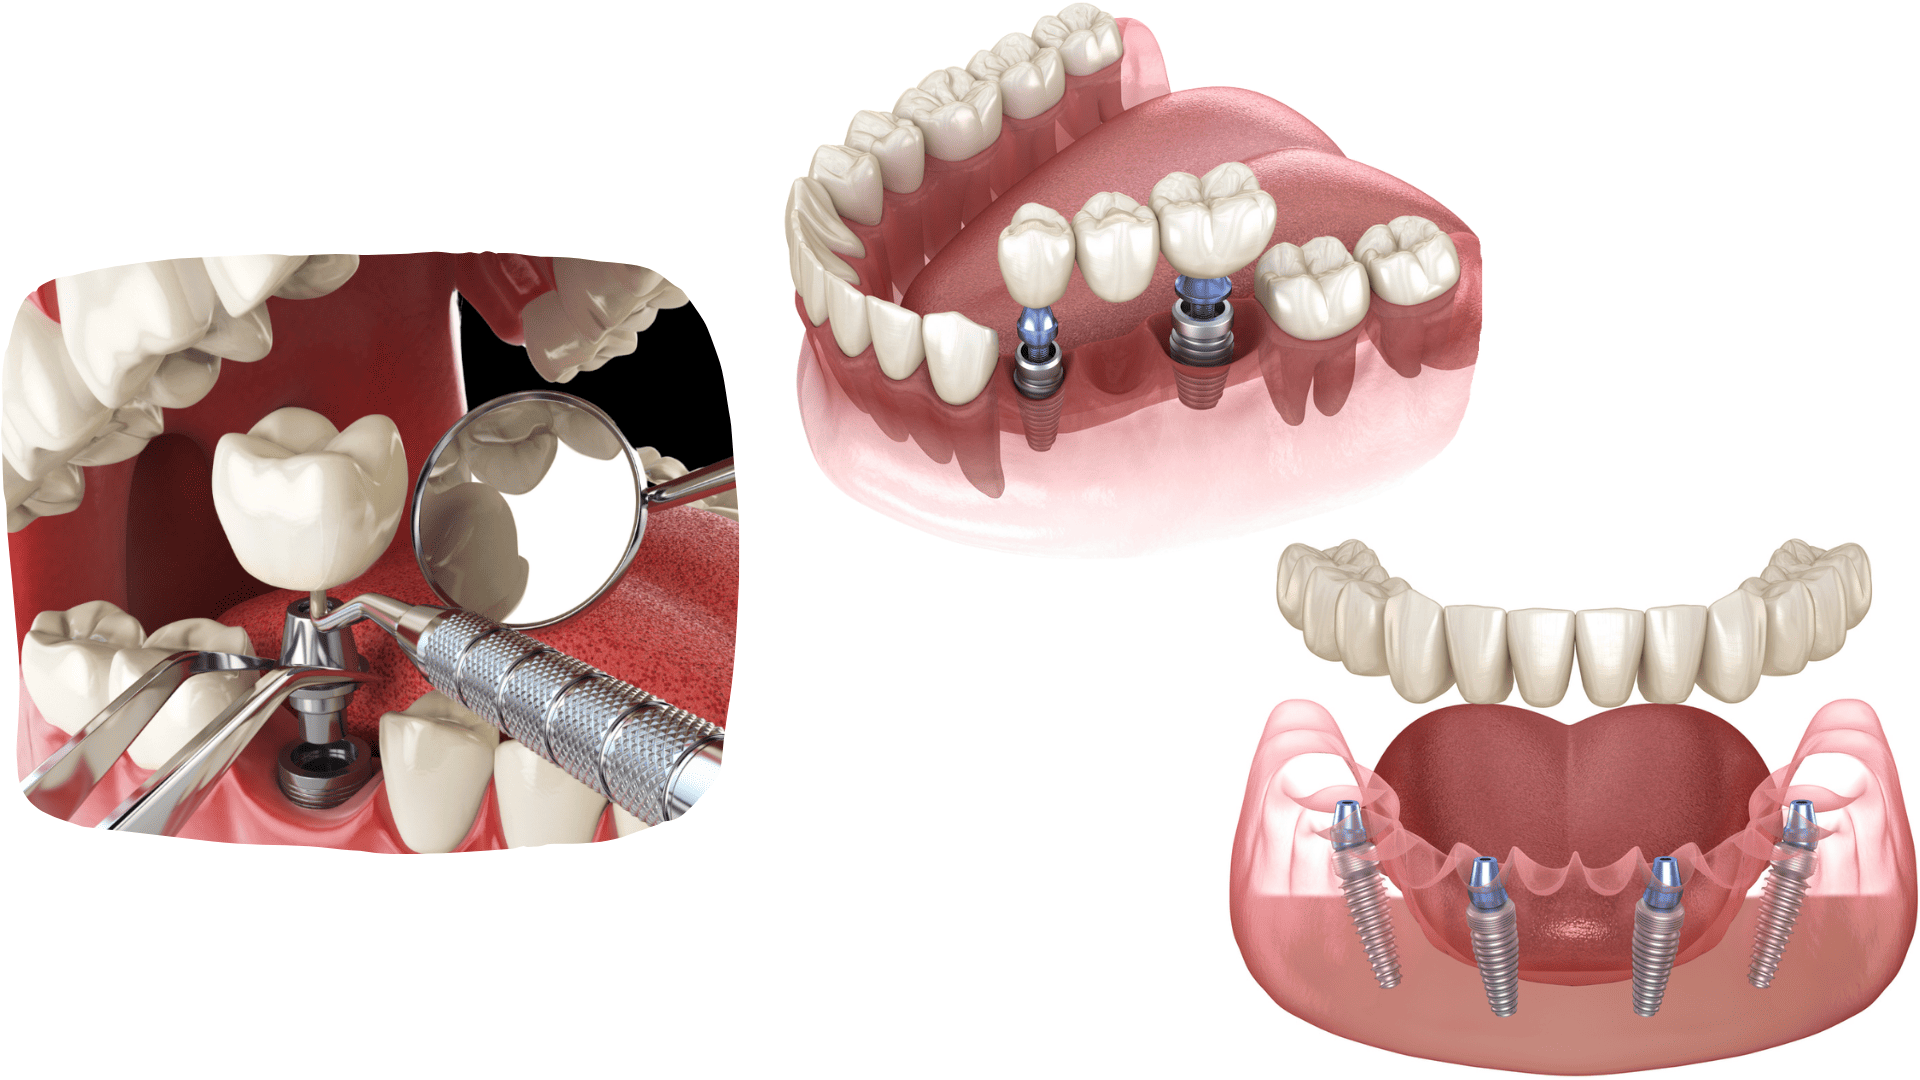

UGRADNJA ZUBNIH IMPLANTATA

Ugradnja zubnih implantata je kirurški zahvat pri kojem se u čeljusnu kost ugrađuje titanski implantat koji zamjenjuje prirodni korijen zuba.

Implantat služi kao stabilan nosač krunica, mostova i proteza. Titan je biološki neutralan materijal koji omogućuje čvrsto i trajno povezivanje implantata s kosti.

Zubnim implantatima moguće je nadoknaditi jedan zub, više zuba ili riješiti potpunu bezubost.

Zubnim implantatima moguće je nadoknaditi jedan zub, više zuba ili riješiti potpunu bezubost.

Zahvat je bezbolan i izvodi se pod lokalnom anestezijom.